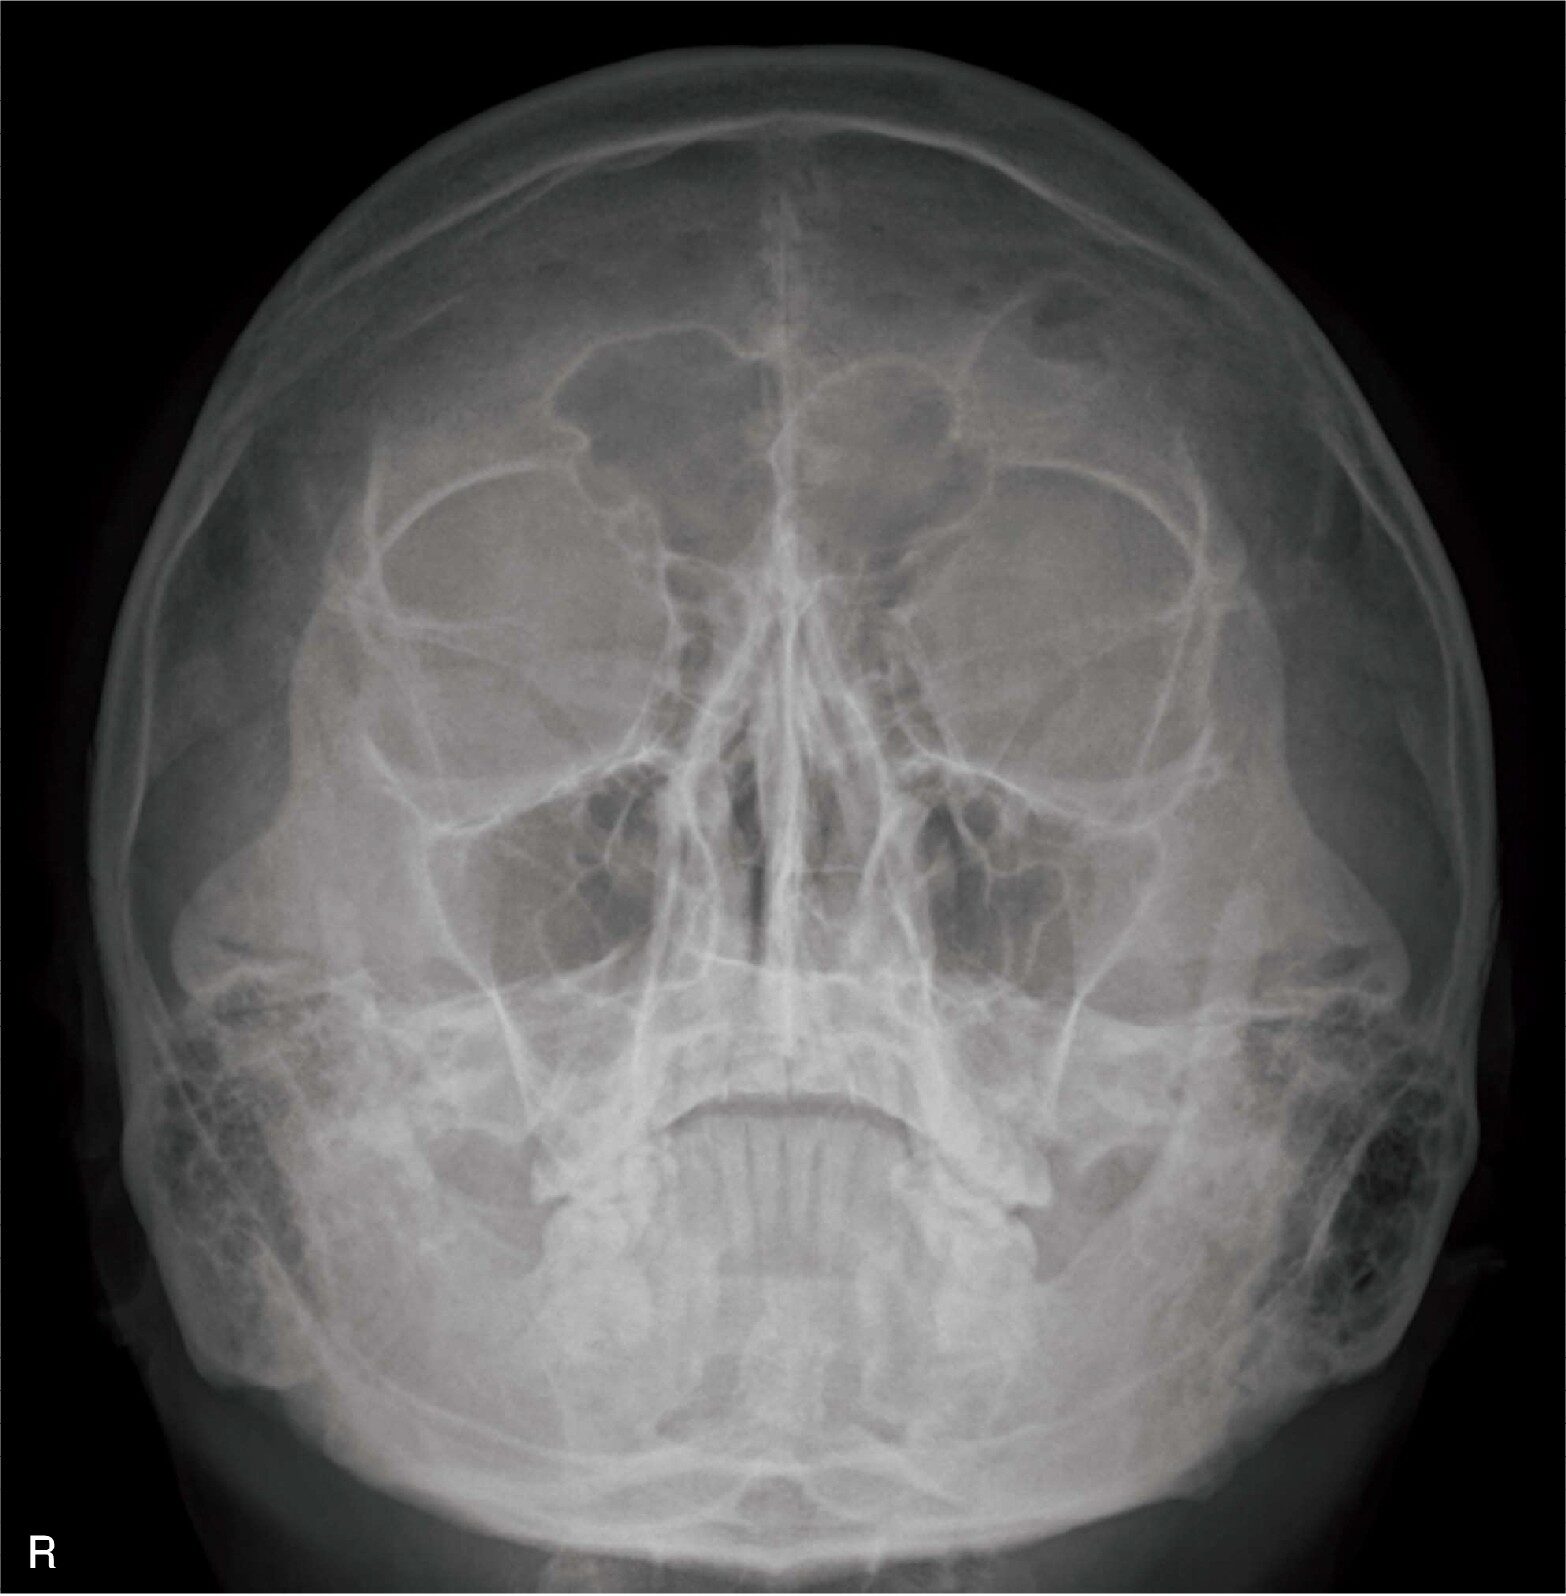

頭部X線写真(別冊No.7)を別に示す。撮影方法で正しいのはどれか。

- 1グリッドは使用しない。

- 2X線の射出点を鼻根とする。

- 340~50

kVの管電圧で撮影する。

- 4中心X線は検出器面に対し垂直に入射する。

- 5ドイツ水平線は検出器面に対し60度とする。